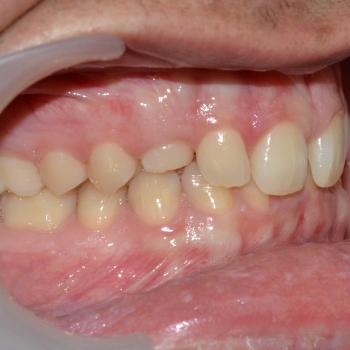

Ádám és édesanyja fogorvosuk javaslatára kerestek fel a felső állcsontban rekedt maradó szemfogak sorbaállításának kérésével. A panoráma röntgenfelvétel elemzése alapján egyértelművé vált, hogy a maradó szemfogak hibás tengelyállása okozta a tej szemfogak perzisztenciáját és a maradó szemfogak előtörésének a hiányát. A szemfogak 30 és 45 fokos dőlésének klinikai képet tovább árnyalták egyéb fogszabályozási eltérések is, mint például a mélyharapás, a nagymetszők közötti rés, illetve jobb oldali második nagyőrlők közötti fordított keresztharapás.

A probléma súlyosságát figyelembe véve, Ádám nagyon bölcsen az önligírozó fém fogszabályozó mellett döntött, melyet bite turbo harapásemelővel és különböző intermaxilláris gumihúzásokkal egészítettünk ki. Az önligírozó fogszabályozó ellenére a kezelés ideje igen hosszú volt. Ennek oka, hogy a szemfogak szájsebészeti feltárása közben derült fény a levontatantó fogak dőlésén kívüli 100-160 fokos tengely körüli elcsavarodására is.